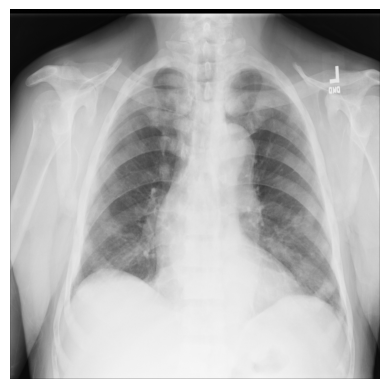

让我们从一个简单的例子开始,只使用ChestX-ray8数据集中的一张X光图像。

文件 — 00000011_001.png — 已为您下载并保存在/tutorial-x-ray-image-processing文件夹中。

1. 使用imageio加载图像

xray_image = imageio.v3.imread(os.path.join(DIR, "00000011_001.png"))2. 检查其形状是否为1024x1024像素,并且数组由8位整数组成

3. 导入matplotlib并在灰度颜色映射中显示图像

import matplotlib.pyplot as plt

plt.imshow(xray_image, cmap="gray")

plt.axis("off")

plt.show()